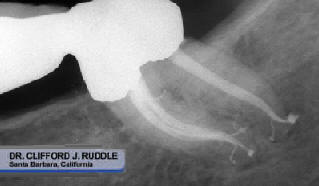

Sistemas

de conductos

limpios y

permeables,

proporcionan el éxito

de la

obturación

3D a largo plazo

(Figuras

11- 14).